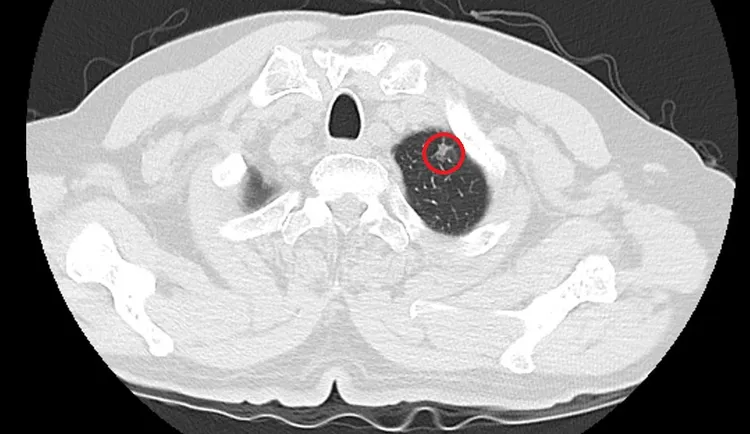

切除可疑肺病灶後,病理報告證實為肺腺癌。光田醫院提供

在進一步發現可疑病灶後,光田醫師胸腔外科陳紀寰醫師立即與患者及家屬溝通,說明目前的手術計畫將進入胸腔處理骨折與積血,同時也建議利用這次機會,直接切除可疑肺病灶,爭取最佳治療時機。手術順利完成後,病理報告證實為「肺腺癌」。所幸是顆小於1公分的早期腫瘤。

陳紀寰醫師說,該名患者屬於肺癌最早期的第一期,是所有肺癌分期中最輕微、預後最好的階段,不僅幾乎無症狀,治癒率極高。也正因為發現得早,處理及時,術後無需接受化療或放療,目前恢復良好,僅需定期追蹤觀察。